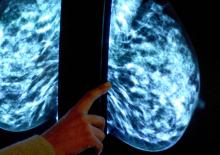

Jun 04, 2018 | Posted by DA | 0 La plupart des femmes atteintes d'un cancer du sein au stade précoce peuvent être en mesure d'évite